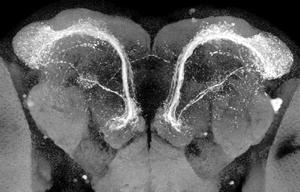

Neuronas del sistema olfativo están implicadas en el Alzheimer y el Parkinson